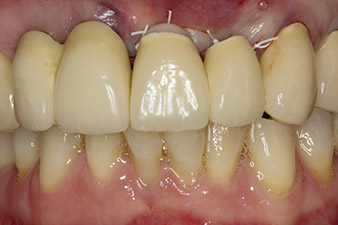

67-годишна пациентка е с ендодонтски проблеми и гингивит около протетичното й възстановяване в горна челюст. След екстрахиране на зъби 21 и 22, планът за лечение е да се поставят импланти с абатмънти като нов мост. Работното поле ще бъде обработено с новия имплантологичен мотор Implantmed на W&H и стабилността ще бъде измерена с интегрирания W&H Osstell ISQ модул.

При първоначалното лечение на пациентката, зъби 21, 22 и 23 са шинирани в корона, вече на 19 години, които са закрепени към имплантите на позиции 12/11 чрез надстройка (Фиг. 2).

Зъб 23 разкрива хоризонтално-коронарна фрактура и е възстановен с коронарно изграждане за временно възстановяване. Планът за лечение е да се постави циркониево-оксиден мост върху съществуващите импланти в позиции 12 и 11 и да се поставят два нови импланти в позиции 22 и 23.